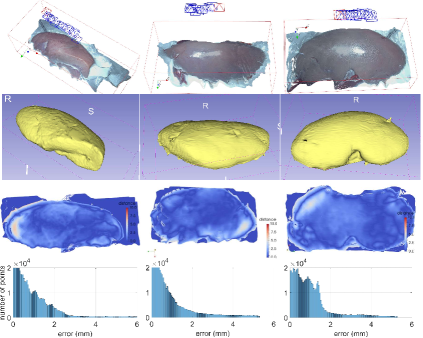

In order to evaluate the quantified accuracy of our 3D reconstruction method, we used the CT imaging of tissues as the gold standard. In this experiment, CT scans of four ex-vivo porcine livers and three kidneys were obtained (Siemens Somatom, Erlangen Germany) with a 0.6 mm resolution at our hospital, and we used the 3D Slicer software to segment the tissue models from the CT images, as shown in Fig. 9. We captured stereo videos of the tissues with the KARL-STORZ stereo laparoscope, the details of which are in Tab. II. Surfaces of livers and kidneys are very smooth and have low textures, but the proposed method was still able to reconstruct the 3D models, as shown in Fig. 7. To quantify accuracy, we registered the 3D reconstructed model with the CT segmentation results by first manually selecting landmarks, such as tissue tips, edge points and other recognizable points, and then refining the registration with the ICP algorithm. As shown in Fig. 7 (a), the root mean square errors (RMSE) with the liver cases are 1.3, 1.1, 1.4 and 2.0 mm respectively. The fourth liver case has a relatively larger error because we used an entire piece of liver and the video was captured at a larger camera-tissue distance. The results on porcine kidneys are shown in Fig. 7 (b), the RMSE of which are 1.0, 1.0 and 1.1 mm respectively. The histograms of errors are also provided in Fig. 7, which show that most points have an error of less than 2mm. It is worth noting that there are multiple sources of errors, including 3D reconstruction error, CT resolution error, CT segmentation error and registration error that contribute to the obtained RMSE in this experiment. In addition, because the livers and kidneys were placed on a textureless plastic sheet and part of the sheet were also included in the 3D reconstructed model, which is difficult to be totally removed (see the tissue edges in the distance maps of Fig. 7), so the quantified error may also include a small amount of the background. Therefore, it is a reasonable assumption that the actual error of our 3D reconstruction method is smaller than the reported RMSE.